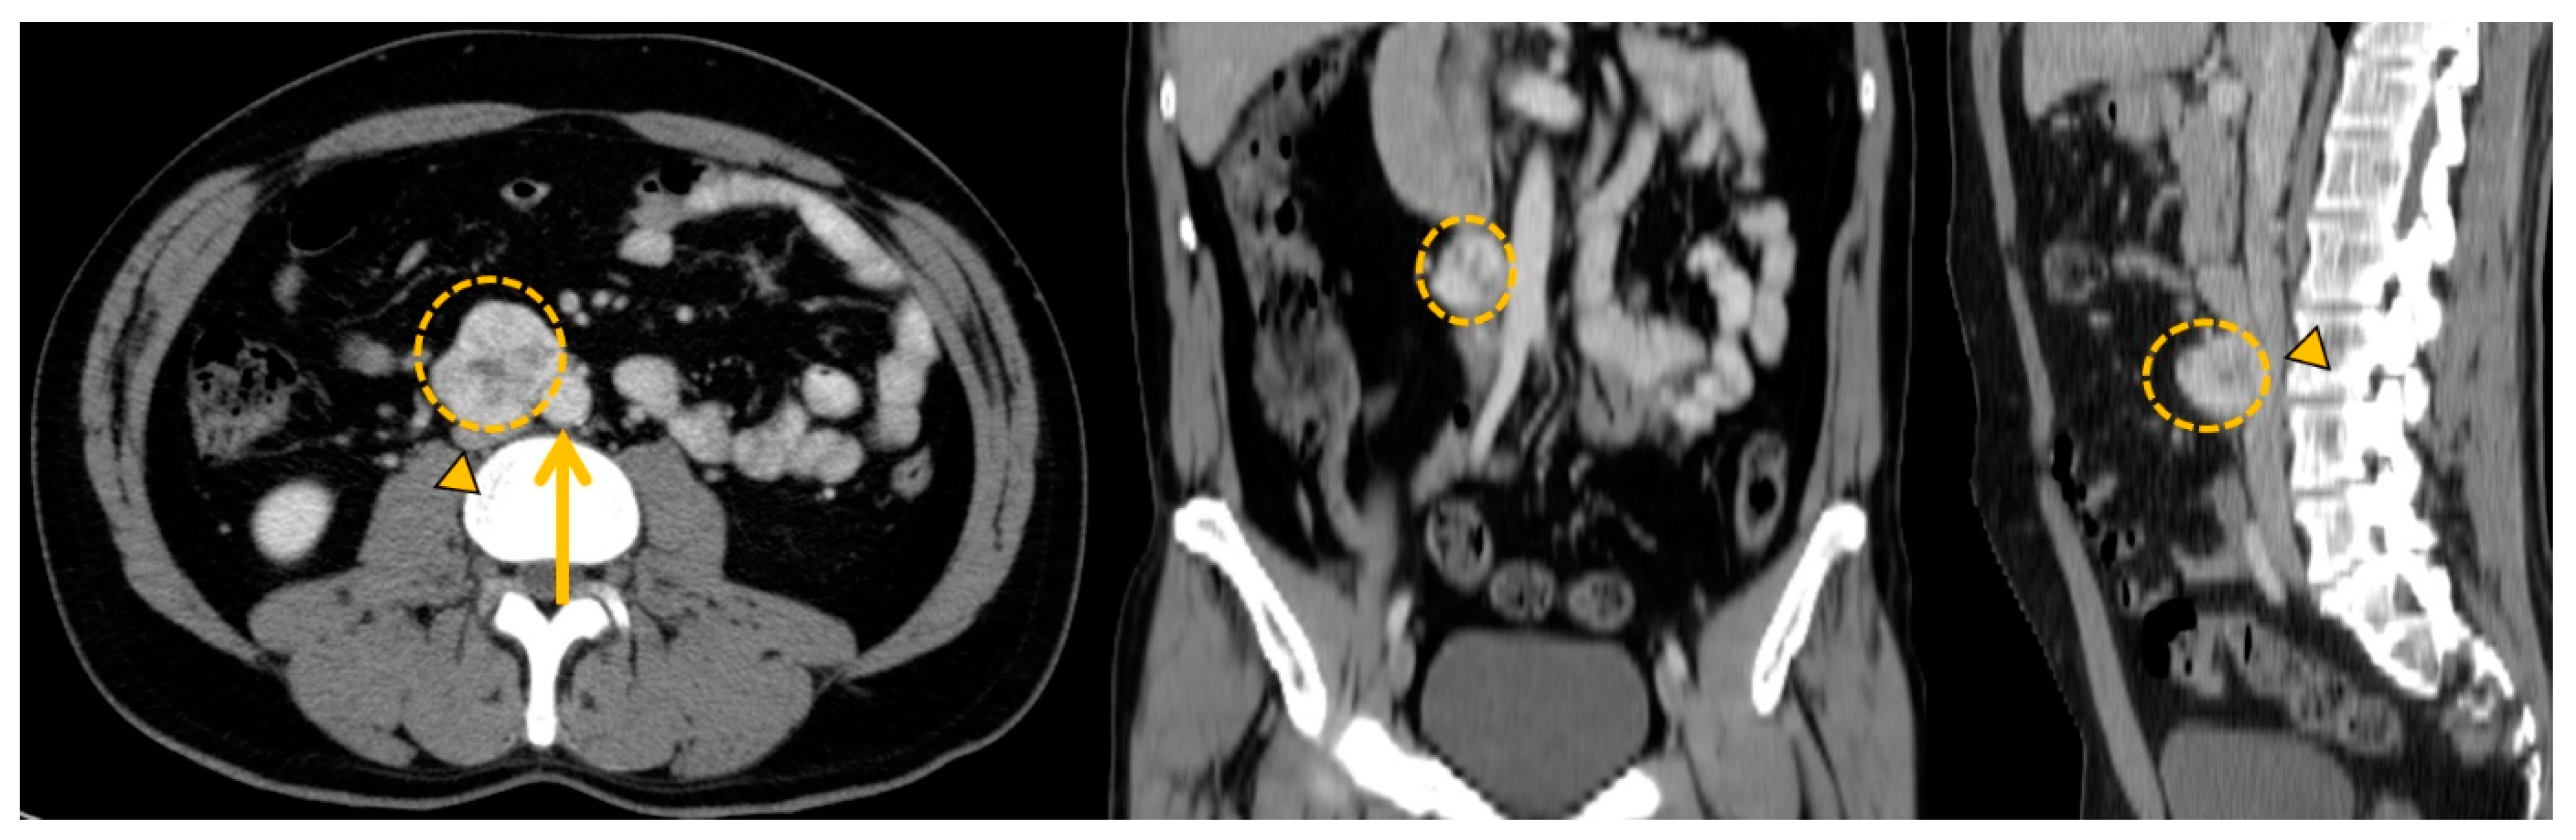

3.4. Pheochromocytomas and Paragangliomas: Variable Morphological Characteristics Using Anatomical Imaging

5. Planning a Surgical Treatment: The Role of Imaging

5.2. Curative Surgical Management: How to Prepare a Surgery?

5.3. Palliative Surgery: The Debulking Strategy Concept